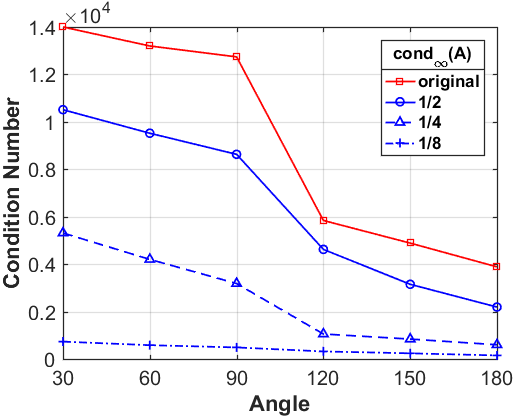

where denotes the number of angles in the angular interval for limited-angle CT reconstruction, denotes the number of units on the detector, and represents the number of pixels of the input image. For CT reconstruction problem (1), the condition number of the system matrix directly affects the stability of the solution [37]. The larger the condition number of the system matrix, the more serious the ill-posedness of the inverse problem, which may result in the degradation of the numerical methods.

Let us define a low-resolution system matrix , the geometric parameters of which are consistent with the system matrix , i.e., and of being the same as , and only the number of the pixels changes. More specifically, we use the equidistant sampling with the down-sampling rate . Then the dimension of the low-resolution system matrix becomes , and the low-resolution image can be expressed by the down-sampling matrix as given below

where is the down-sampled image and is a diagonal matrix with diagonal elements being either 1 or 0. Then we can arrive at the main theorem supporting our observation that a low-resolution problem has better numerical stability.

Next, we numerically compare the condition numbers of the system matrices for both the low-resolution and original reconstruction problems by 1-norm, 2-norm and -norm, respectively. As shown in Fig. 8, we can observe that the condition numbers of the low-resolution reconstruction problem are much smaller than the original reconstruction problems for different scanning angles, which are consistent with our theoretical analysis. In fact, larger condition numbers allow for undesired solutions, which also numerically satisfy the forward model (1). More importantly, the constraint in our model (2) can help to find better solution from the null space, which has already been perfectly demonstrated by our numerical experiments.

What is more, as shown in Table III, IV and V, the smaller the down-sampling rate, the better the reconstruction result. Since the quality of the image prior decreases as the resolution decreases for the limited-angle reconstruction problems, there is a trade-off between the resolution and the quality. Thus, we track the relationship between the resolution of the low-resolution image priors and the performance of our LRIP-net. As shown in Fig. 9, the best reconstruction results are obtained using the low-resolution image prior with down-sampling rate . Although the smaller the condition number of the system matrix, the better the numerical stability of the solution, it does not mean that the better the performance of our LRIP-net.